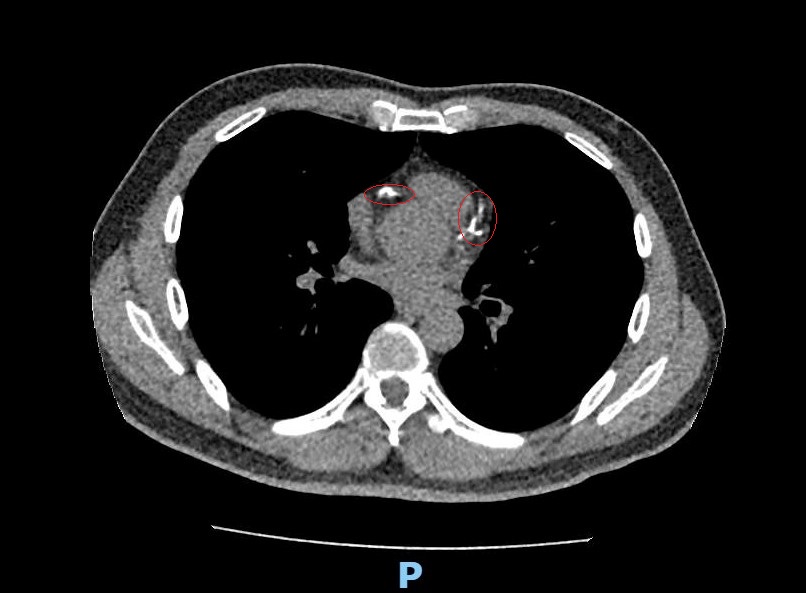

圖說:部彰以低劑量斷層掃瞄為林先生檢查 意外發現他的血管鈣化嚴重

部彰李學林醫師表示,林先生日前接受肺癌篩檢時意外發現心血管鈣化,但無法確認是血管內或血管外鈣化。因患者平時已出現胸悶症狀,進一步做心臟冠狀動脈電腦斷層,確認為3條主要冠狀動脈血管內鈣化狹窄達85%以上,若未及時處理,隨時可能引發急性心肌梗塞。

李學林表示,要看出心血管鈣化情況可以靠心臟冠狀動脈電腦斷層掃描,快速、無侵入性地檢測出心血管的鈣化程度,但必須自費且費用不低,如果能先做LDCT,不僅能篩檢肺癌,還能了解心血管的鈣化情況。政府目前針對「具肺癌家族史」、「具重度吸菸史」兩大肺癌高風險族群,補助每兩年一次的免費LDCT,一般人則需自費篩檢,現今很多人在安排健檢時也會將LDCT納入項目,成了健檢趨勢。